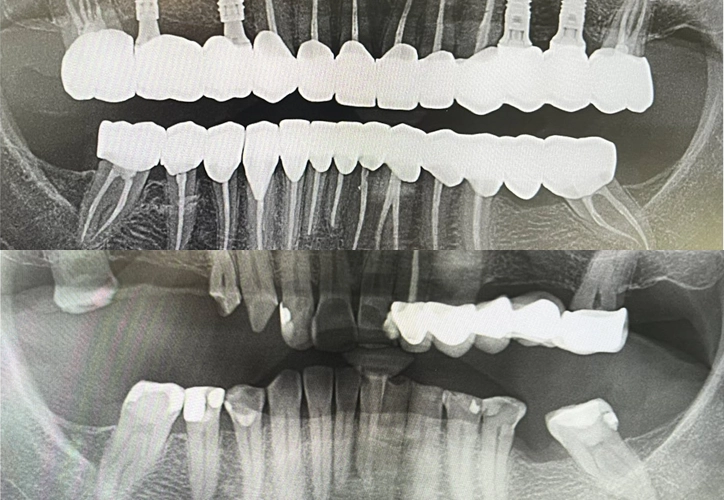

Tratament:

Endodonție si protetică dentară : Dr. Achim Borșanu

Chirurgie implantologie: Prof.Dr. Emanuel Bratu